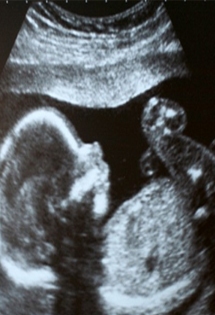

Nuchal translucency (NT) refers to an ultrasound measurement of the back of the fetal neck, which can be done from approximately 11 through 13 weeks of pregnancy. First-trimester screening combines the NT measurement with the results of a blood test, your age, and your ethnic background.